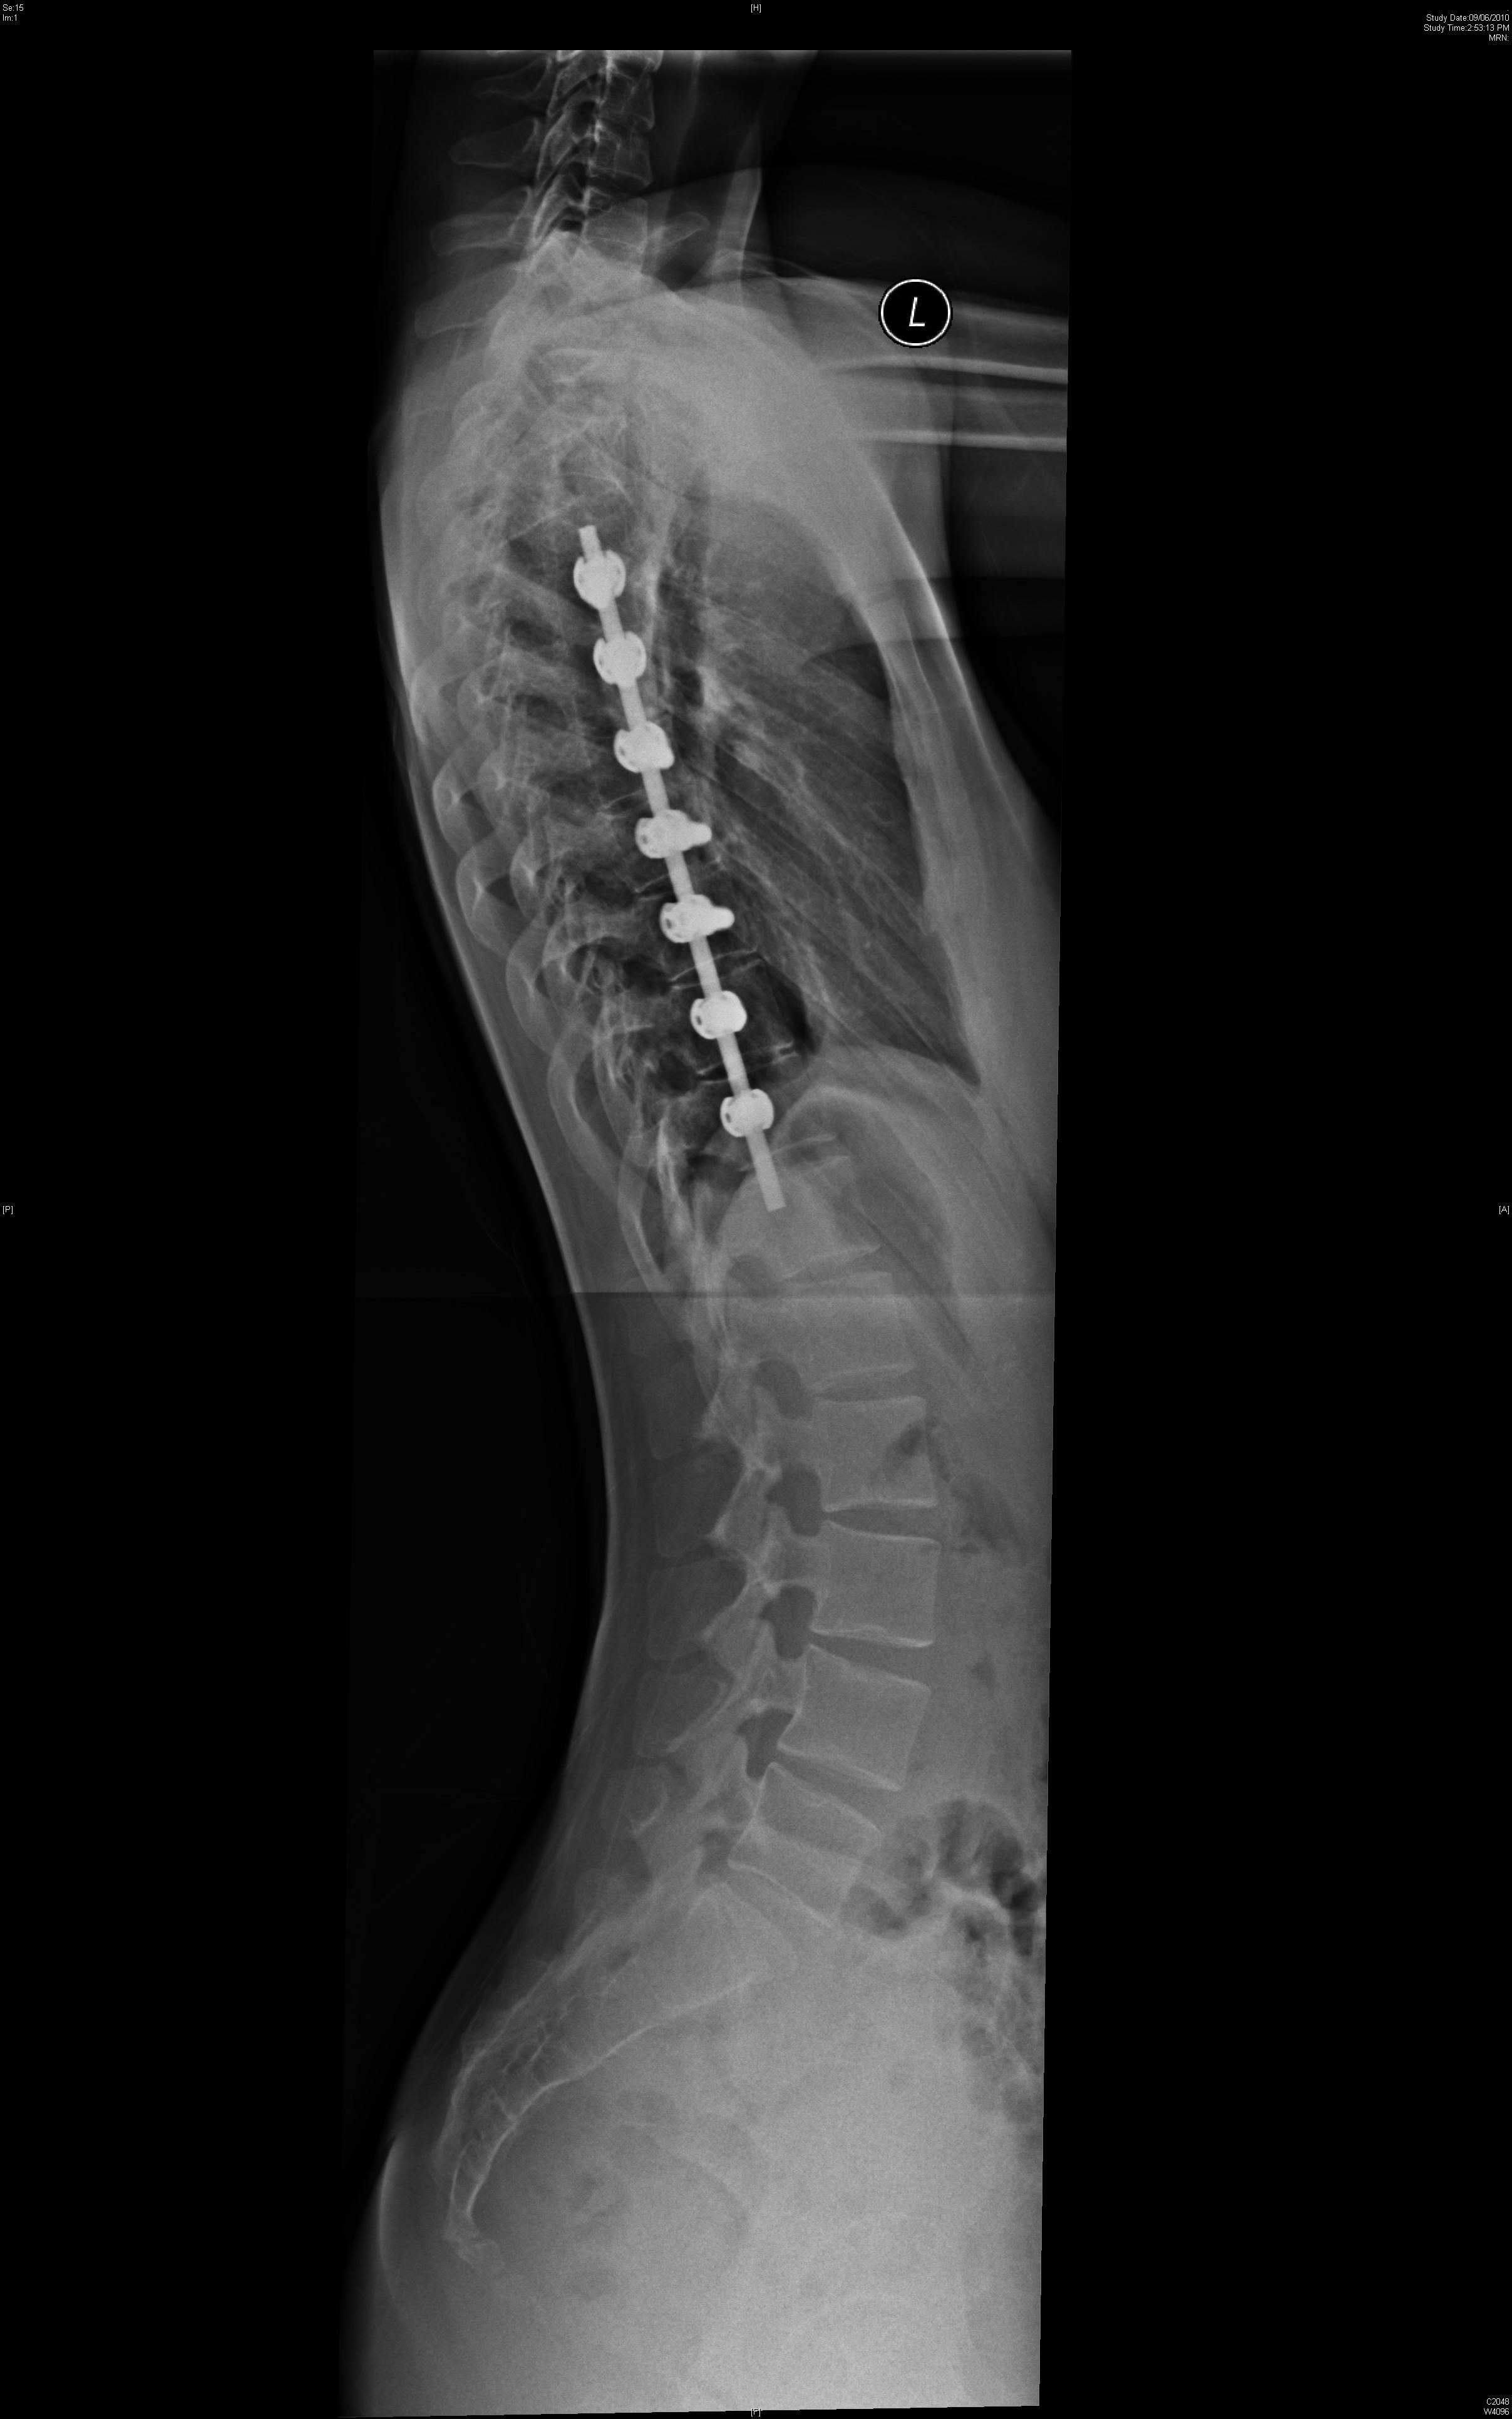

Surgical treatment for degenerative spine disease has traditionally been spinal fusion. Unfortunately, there are a number of drawbacks to spinal fusion. Firstly, the bone may not be able to heal or fuse. The average success rate of fusion is approximately 80%. Failure of the bone to fuse may be associated with continued symptoms. Secondly, fusion will cause stiffness

and decreased motion of the spine. Thirdly, spinal fusion will cause more stress to be transferred to adjacent levels. This increased stress at the adjacent level may cause further degeneration at the adjacent levels which may lead to additional spine surgery.

Artificial disc replacement has been developed as an alternative to spine fusion. The introduction of the total disc replacement aims to relieve patient symptoms while preserving motion at the operative spinal level. The advantage of preserving motion is to minimize the stress at adjacent levels and thereby decrease the risk of degeneration of the adjacent segment.

Currently artificial disc replacement can be used for the lumbar or the cervical spine. Many different models have been developed. The majority consists of two metal plates that have teeth to anchor the implant onto the bone of the vertebral bodies. Between the two plates is a metal core or a plastic core made up of polyethylene that allows for motion. Figure 1 shows a lumbar artificial disc replacement. Figure 2 shows a cervical artificial disc replacement.

The technique to insert an artificial disc (whether in the neck or low back) is routine and safe. For the cervical spine it involves going from the front of the neck. For the lumbar spine, it involves going through the abdomen. The procedure begins by removing the gelatinous disc between the vertebrae. Once the disc is removed, two metal plates are pressed into the bony endplates above and below the space now vacated by the disc. Metal spikes hold these plates in place on the bone. Eventually bone will grow over and around the metal plates. In between the metal plates is a metal or plastic core made of a polyethylene. Figure 3 shows the artificial disc placed in the spine.